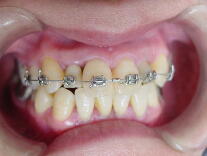

B、部分矯正の後、セラミック冠で治療した症例(上顎前歯部のみ治療)

![]() ![]() ![]()

奥歯のかみ合わせは比較的問題なかったので上の主訴のみ治療。上の前歯を治療するこ

とによって下の前歯も自然に良い位置に移動しました。歯並びを改善することにって歯肉 状態も改善されたことに注目してください。